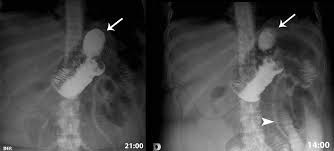

Durante los procedimientos bariátricos, la radiología interviene a través de técnicas como la fluoroscopia. Esta técnica permite a los cirujanos visualizar en tiempo real las estructuras internas, asegurando la precisión de la cirugía y minimizando los riesgos.

Después de la cirugía, la radiología es esencial para el seguimiento. Los estudios de imagen como las radiografías y las TC son fundamentales para evaluar la correcta posición de los dispositivos implantados, como las bandas gástricas, y para identificar posibles complicaciones, como fugas o bloqueos.

Las complicaciones postoperatorias, aunque poco frecuentes, pueden ser graves. La radiología interviene rápidamente para diagnosticar problemas como obstrucciones intestinales, hernias internas o úlceras. Las imágenes obtenidas son críticas para guiar las decisiones clínicas y, si es necesario, las intervenciones quirúrgicas adicionales.